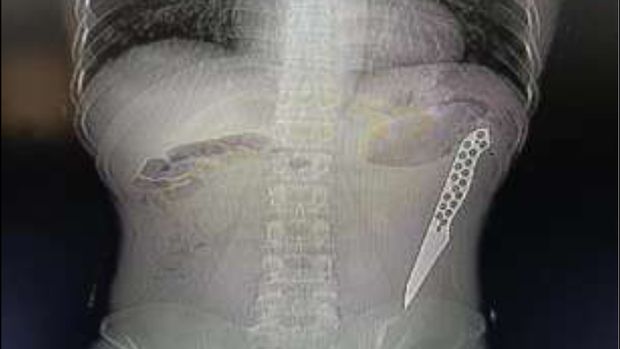

Hasil CT scan menunjukkan pisau itu berada di usus besar di regio lumbal kiri, atau daerah pinggang kiri. Dokter lantas melakukan operasi laparotomi darurat untuk mengeluarkan pisau tersebut.

Penampakan pisau tertanam di tubuh pasien. Foto: International Surgery Journal |

Pisau berhasil dikeluarkan, dokter tidak menemukan tanda radang selaput usus, dan usus lalu ditutup secara primer. Panjang pisau yang berhasil diangkat sekitar 7 inci atau 17,78 cm. Pasca operasi, kondisi pasien berangsur-angsur membaik.